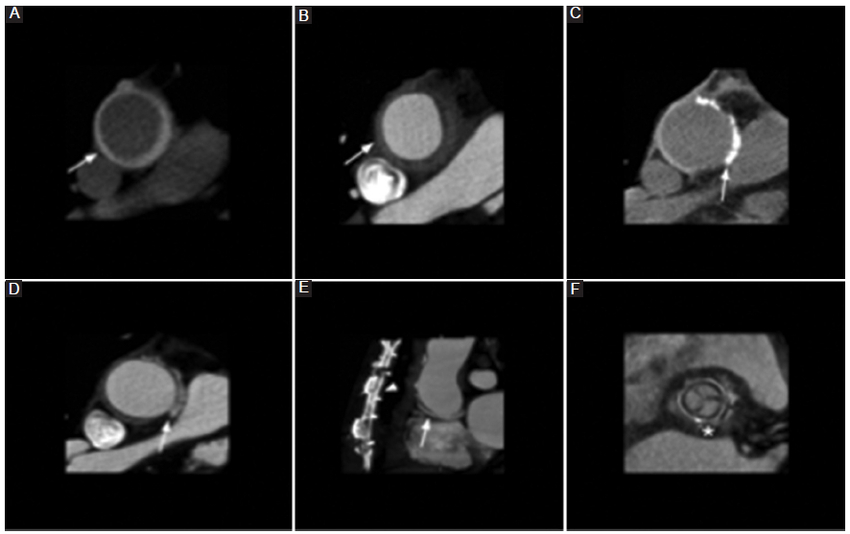

Cirugía de Bentall de Bono

Fue desarrollada para pacientes con enfermedad valvular y dilatación de los senos de Valsalva cuyas paredes eran demasiado vulnerables para permitir la sutura de la prótesis. Consiste en el uso de un injerto compuesto que contiene una prótesis valvular aórtica y el reemplazo protésico de la arteria aorta ascendente, a la que se reimplantan las arterias coronarias nativas (Fig. 2) (2,3,5. Consecuente al desarrollo relativamente común de pseudoaneurismas en los sitios de anastomosis de las arterias coronarias nativas, se produjeron mejoras en la técnica que llevaron a la creación del procedimiento de Bentall modificado o «botón de Bentall», en el que se adquiere un botón coronario de la aorta que contiene el ostium de las arterias coronarias junto a esta, facilitando así la anastomosis del injerto (Fig. 3) (2,3,5. En la actualidad, el botón de Bentall es el método preferido para la reparación de la raíz aórtica. A pesar de estos últimos cambios, no está exento de la formación de pseudoaneurismas en los sitios de la anastomosis aórtica distal2,3,5.

Cirugía de Cabrol

La técnica de Cabrol se desarrolló como una alternativa al procedimiento de Bentall modificado en pacientes con disección aórtica, aneurisma aterosclerótico e imposibilidad de realizar la técnica de Bentall por aterosclerosis grave que impide el empleo de botones aórticos, así como el compromiso grave de la arteria coronaria proximal. Primero, los ostia coronarios se anastomosan a un conducto protésico en una anastomosis término-terminal. A su vez, este conducto está anastomosado al injerto aórtico ascendente en una anastomosis latero-lateral, típicamente posterior al injerto (Fig. 4) (2,3,5. La apariencia posoperatoria normal de un conducto retroaórtico puede asemejarse a un colgajo de disección aórtica, por lo que el conocimiento de la técnica quirúrgica y su antecedente es importante al momento del informe imagenológico2,3,5.

Cirugía de Ross

Esta operación fue ideada para implementarse en niños porque el autoinjerto pulmonar crece con el niño, aunque también puede ser utilizada en pacientes de cualquier edad6.

En el procedimiento de Ross, la válvula aórtica nativa y la raíz aórtica son reemplazadas a 1 cm distal al origen de la arteria coronaria derecha, lo que a su vez permite inspeccionar el estado de la válvula aórtica, la raíz aórtica y el tracto de salida del ventrículo izquierdo durante el acto quirúrgico7. La válvula pulmonar y la porción proximal de la arteria pulmonar del propio paciente se fijan al tracto de salida del ventrículo izquierdo y al anillo aórtico con múltiples suturas de poliéster. A esta arteria aorta tratada se le reimplantan las arterias coronarias, las cuales serán reubicadas en función de la válvula, pudiendo ser esta última subcoronaria, subcoronaria con preservación del seno no coronario, cilíndrica o raíz completa. Finalmente, se restablece el flujo de la arteria pulmonar a través de un injerto sintético o bioprotésico (Figs. 5 y 6) (6,7.

Al igual que otros procedimientos, la cirugía de Ross puede tener complicaciones, entre las que se mencionan el aumento de la regurgitación aórtica y la dilatación progresiva del autoinjerto pulmonar como principales limitaciones6,7.